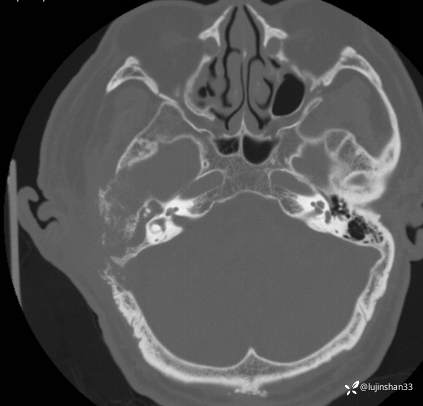

CT:

简要病史:患者2022年10月掏耳后出现右耳疼痛,流水,伴血性分泌物,伴听力下降,无头痛头晕,无口角歪斜,自行购买滴耳液及口服罗红霉素,效果不佳。后右耳痛加剧,偶需止疼药治疗。后于XXXXXX医院行中耳乳突CT检查示“右耳恶性肿瘤?坏死性外耳道炎?”颅脑磁共振平扫示“脑内多发缺血灶、梗塞灶,脑白质疏松,脑萎缩、右中耳恶性占位。”建议上级医院治疗。2023-4-13就诊于我科门诊,行右外耳道病理活检示“鳞状上皮黏膜慢性炎伴急性炎,可见较多炎性坏死,部分上皮增生明显伴不典型增生,小灶上皮呈重度异型增生伴癌变。”建议手术治疗。今患者为求进一步诊治,门诊以“颞骨占位(右)“收治入院。